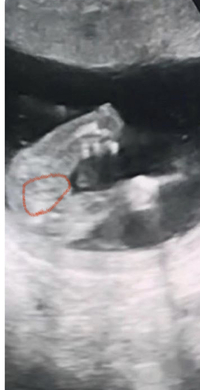

21週の赤ちゃんの正面のエコー写真です 先生に女の子って言われましたが 女の Yahoo 知恵袋